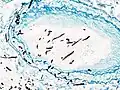

On microscopy, Aspergillus species are reliably demonstrated by silver stains, e.g., Gridley stain or Gomori methenamine-silver.[27] These give the fungal walls a gray-black colour. The hyphae of Aspergillus species range in diameter from 2.5 to 4.5 μm. They have septate hyphae,[28] but these are not always apparent, and in such cases they may be mistaken for Zygomycota.[27] Aspergillus hyphae tend to have dichotomous branching that is progressive and primarily at acute angles of around 45°.[27]

Aspergillus vesicle (HE stain)